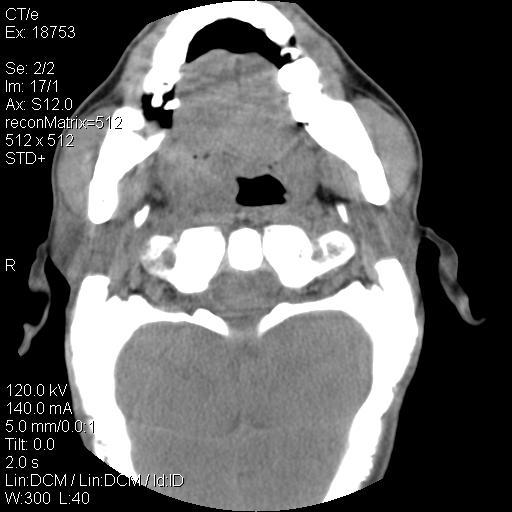

标题: CT21693:男 58岁 右侧咽部疼她2天余 PE:右侧扁桃体肿大 压痛 [打印本页]

标题: CT21693:男 58岁 右侧咽部疼她2天余 PE:右侧扁桃体肿大 压痛

右化脓性扁桃体炎症伴咽后壁脓肿形成.

以下是引用zjzjr在2009-8-19 21:07:00的发言:[br]右化脓性扁桃体炎症伴咽后壁脓肿形成.